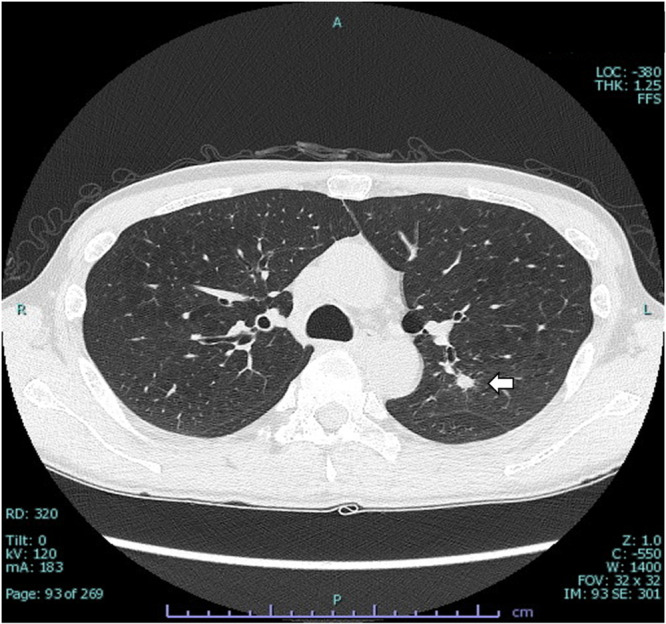

Case presentation: We present a case of a 51-year-old man with schizophrenia who developed CLIA complicated by IPA. The patient, diagnosed with treatment-resistant schizophrenia, was started on clozapine, but 9 months later he presented with fever, cough, leukopenia, and neutropenia. Clozapine was discontinued, and empirical treatments with cefepime and filgrastim were initiated. Serum β-D-glucan and Aspergillus galactomannan antigen tests were positive, and chest CT showed well-circumscribed nodules, leading to a probable diagnosis of IPA. Antifungal therapy was switched from micafungin to voriconazole according to guidelines. His neutropenia and fever improved, and he was re-transferred to a psychiatric hospital.